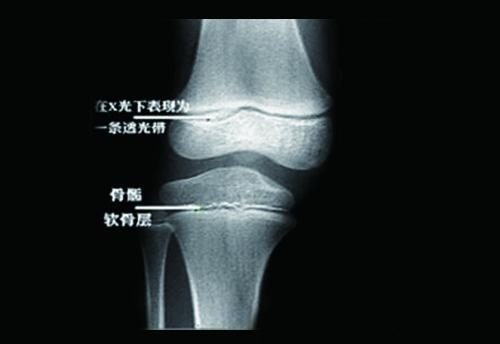

骨骺与骨干之间有一层软骨层,医学上称之为骺软骨 ( 骨骺线).

骨骼和骨干之间是干骺端,干骺端和骨骺之间有一层软骨结构(骨骺线),这

长骨按其部位分为骨干和骨骺,在骨骺和骨干之间的软骨是骺软骨,骺软骨

骺软骨能不断增生,又不断骨化,使骨的长度增加.